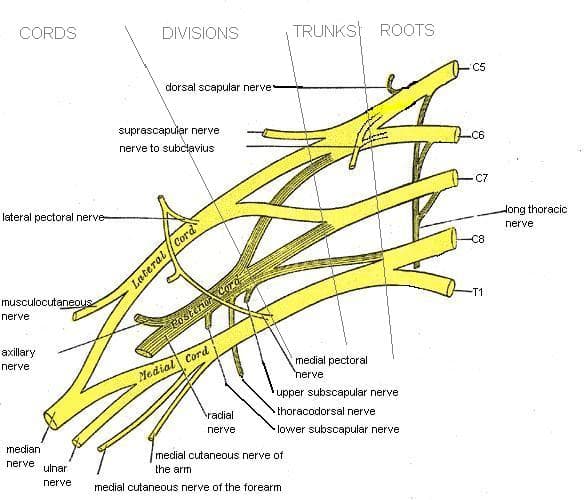

A review of the detailed and complex anatomy of the brachial plexus is well beyond the scope of this article. As a quick summary, those cervical and thoracic nerves combine to form nerve trunks, and the trunks become divisions, with some of the original nerve fibers staying together and some splitting up. Then again, the divisions become cords and then branches which become the peripheral nerves providing sensation and movement to the arms.

Diagram showing the brachial plexus. Note the combinations and divisions that end up becoming the nerves of the shoulder, arm and hand.

By Mattopaedia at en.wikipedia [Public domain], from Wikimedia Commons